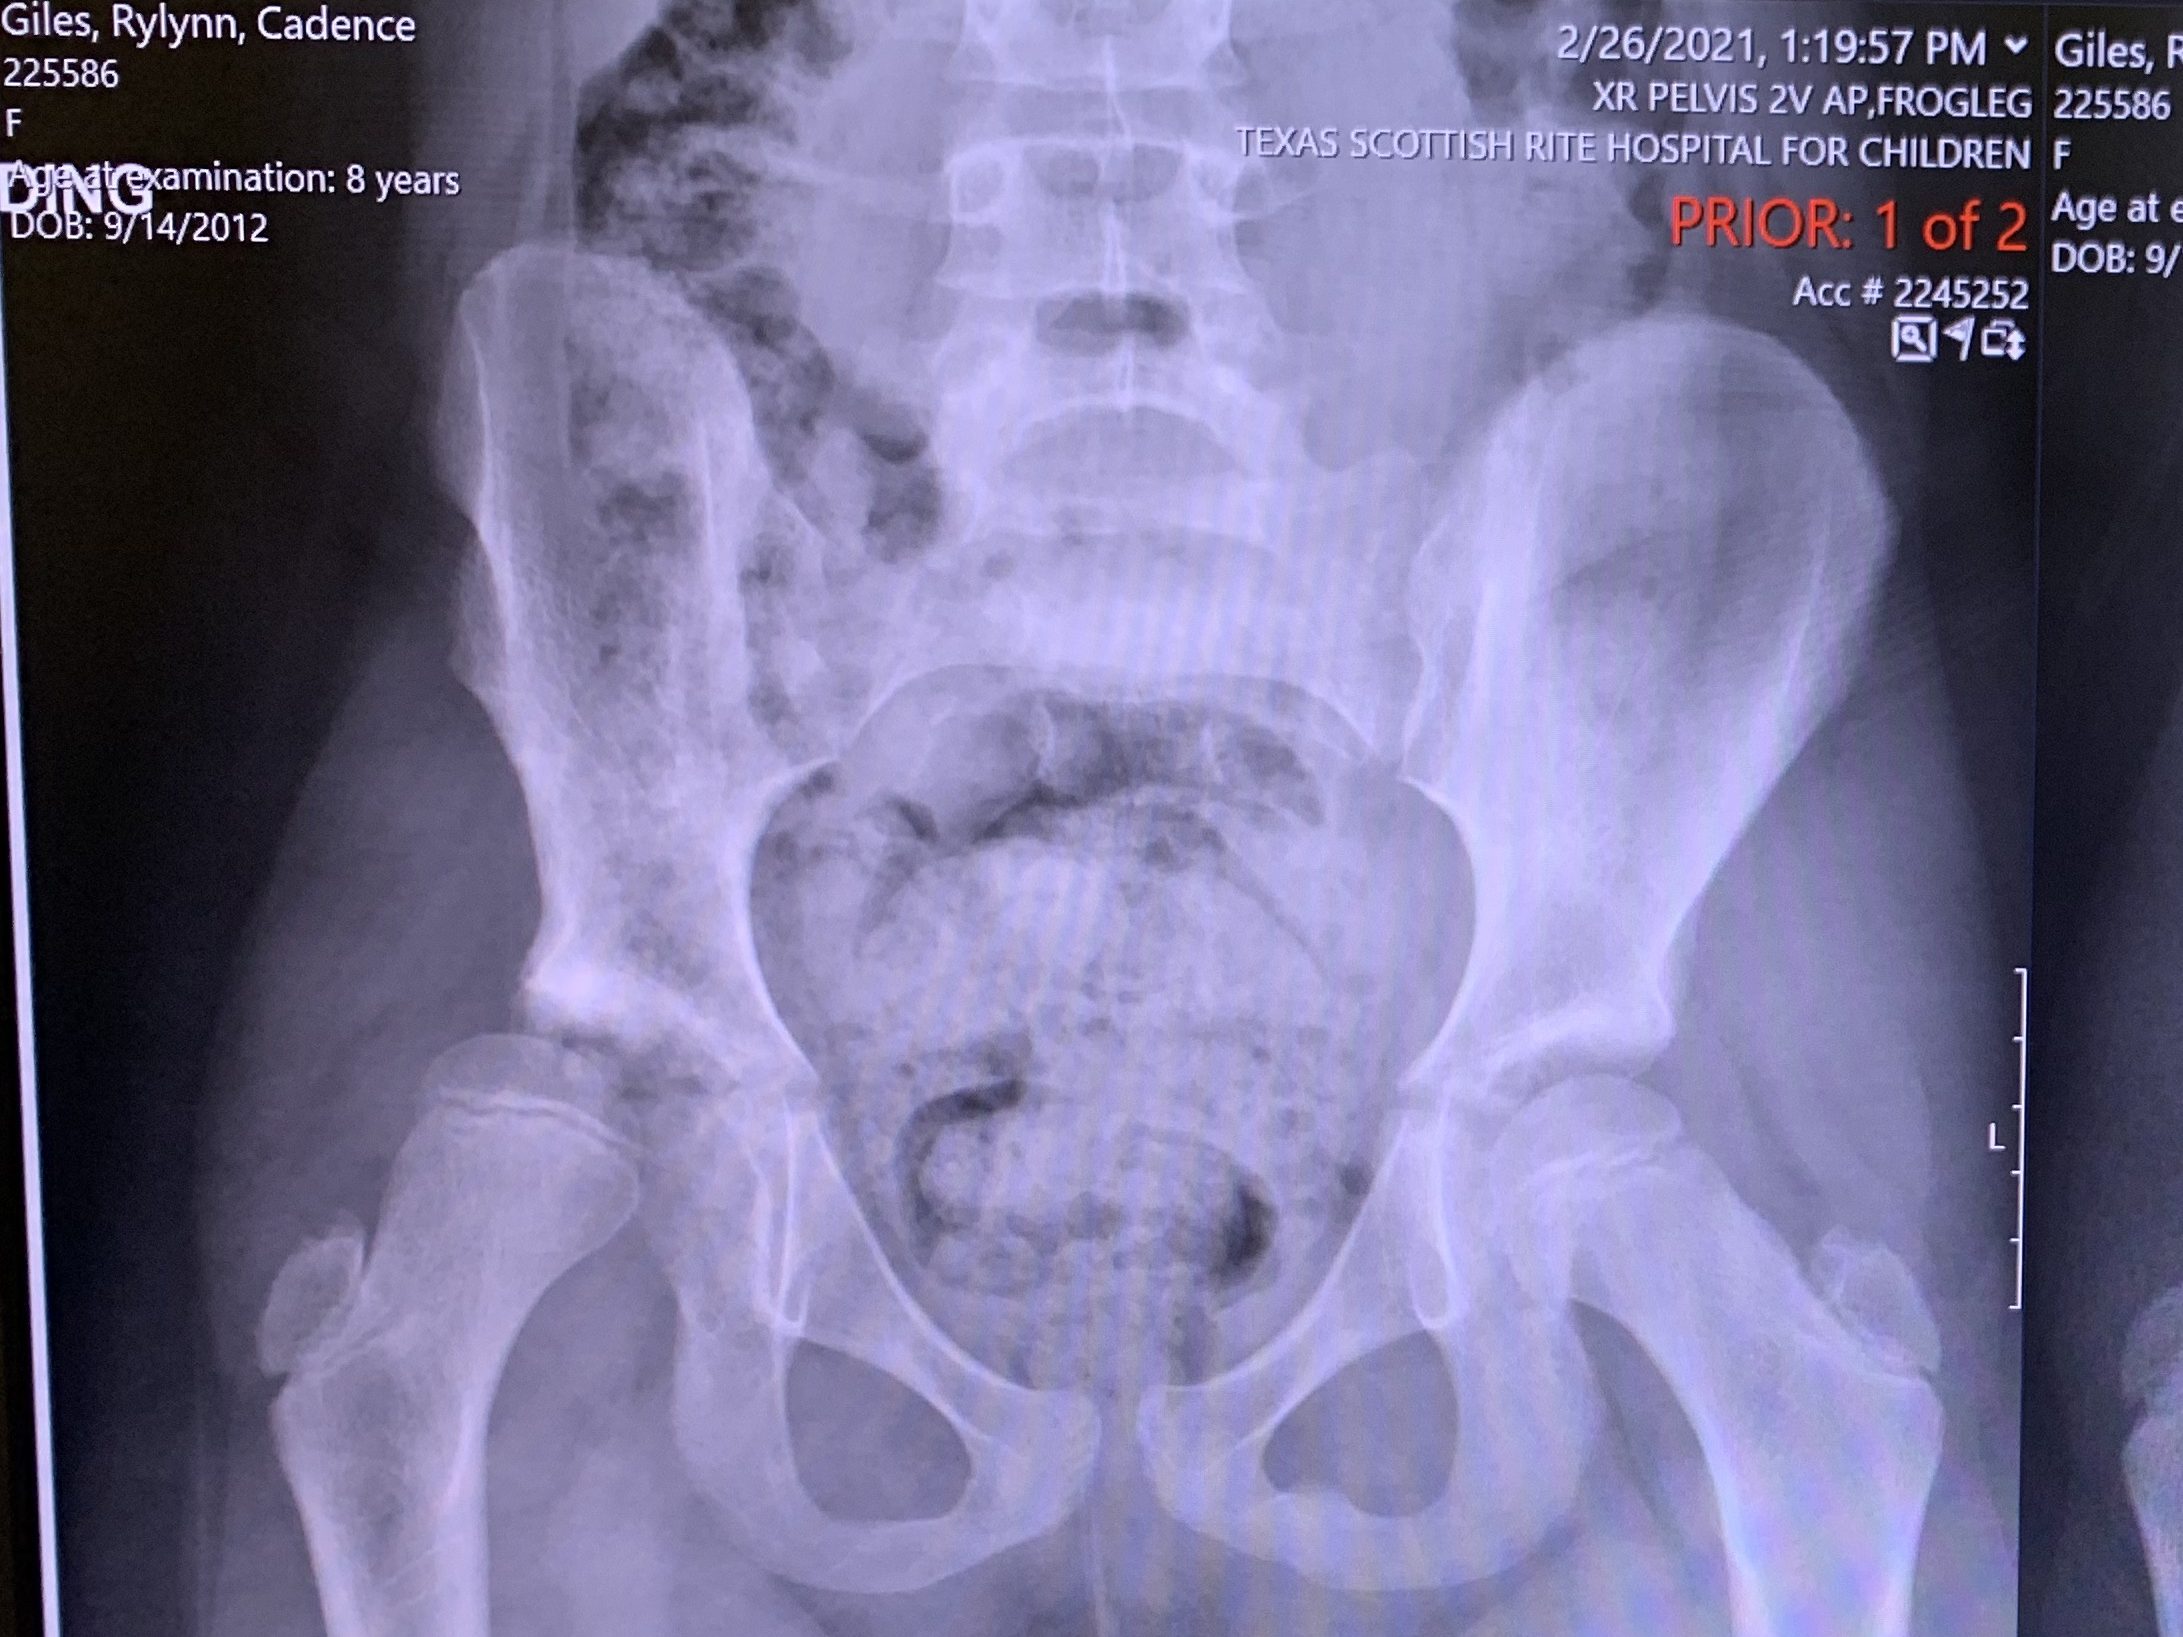

We are just two days away from being halfway through the six weeks. Rylynn has started telling people that she’s out of the pain stage and she is now in the bored stage. Thank the Lord, the hardest part is behind us. The pain stage was tough for sure. I much prefer the bored stage.…

I write this from Rylynn’s bedside at 4:45am. The first night after surgery is brutal, no way around it. It’s all about trying to figure out pain control. I’ll tell you, that is not as easy as it sounds. It’s nurses coming in every two hours to check vitals and test the feeling in her…